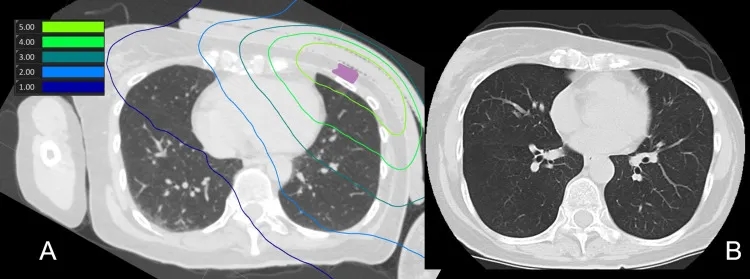

结果显示:BNCT后1天、3天、7天、30天、60天、90天CT扫描,均未显示放射性肺炎迹象,下图2为肺部剂量分布及治疗后90天CT扫描)。

▲图源“Cureus”,版权归原作者所有,如无意中侵犯了知识产权,请联系我们删除

①图2 A:BNCT(肺部)剂量分布图。

②图2 B:治疗后90天CT扫描,未观察到放射性肺炎的迹象。